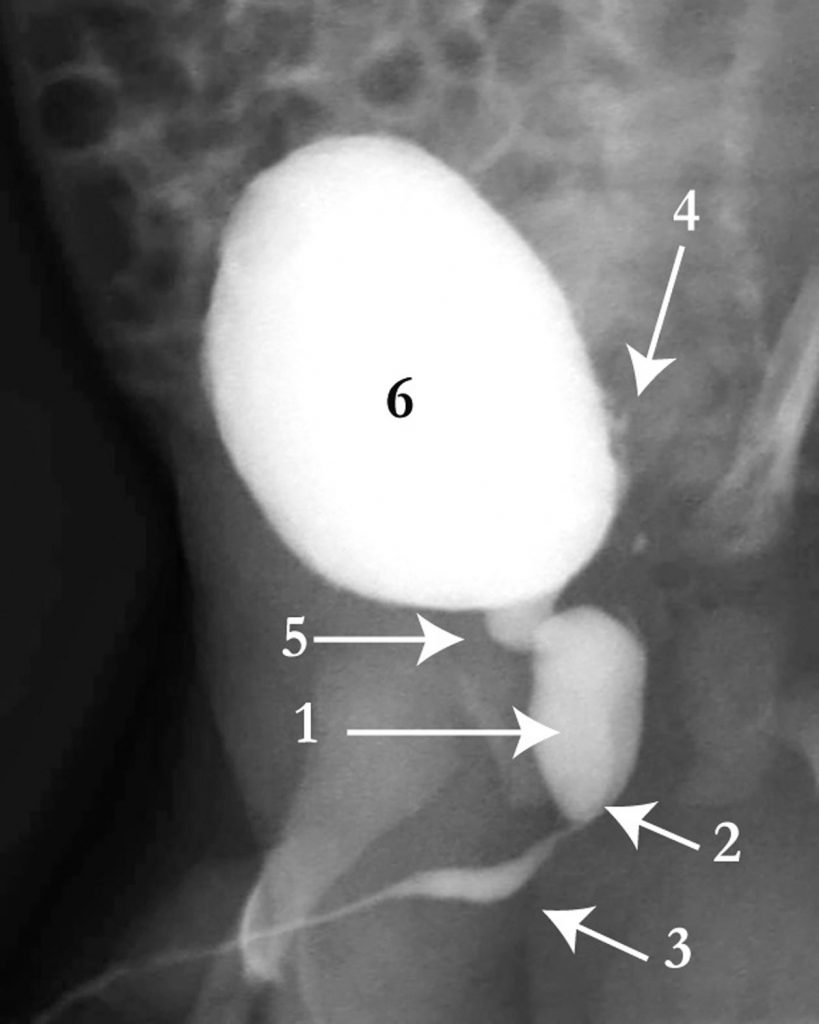

La cystographie démontre une disparité de calibre entre l’urètre postérieur et l’urètre bulbaire (figure 110.2). Elle visualise souvent une vessie de lutte et un reflux vésico-urétéral.

Fig. 110.2 Cystographie au temps mictionnel.

Il existe une disparité de calibre entre l’urètre postérieur (1) et l’urètre bulbaire (3), les valves siégeant à la partie inférieure du veru montanum (2). Il existe des irrégularités pariétales (4) au niveau de la vessie (6) traduisant une « vessie de lutte ». Le col vésical est normal (5).

Source : CERF, CNEBMN, 2022.